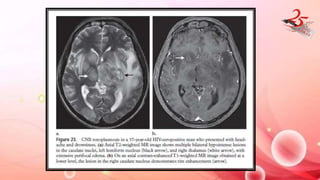

Figure 19. Basilar artery occlusion in a 61-year-old

man with ocular signs and severe obtundation. (a)

Diffusionweighted MR image shows bilateral

hyperintense areas in the paramedian thalamus

(arrows). (b) Timeof- flight MR angiogram clearly

depicts occlusion of the rostral portion of the

basilar artery (arrow). (c, d) Noncontrast CT scans

obtained 3 days later show bilateral subacute

infarcts of the thalamus (arrows in c) and an

infarct in the right cerebellar hemisphere

(arrow in d).